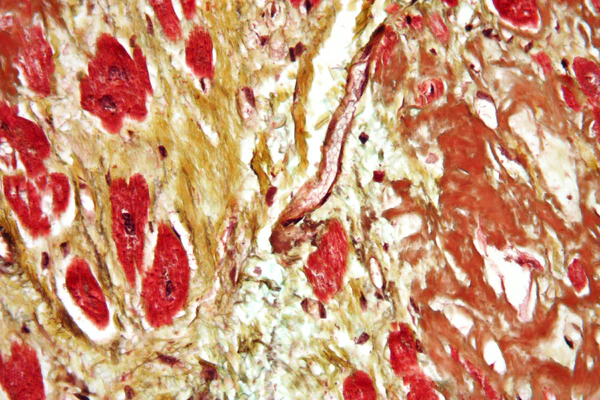

Одной из наиболее опасных форм течения ИБС и одной из основных причин смерти является инфаркт миокарда (ИМ) — некроз (гибель) участка миокарда вследствие резкого ухудшения коронарного кровотока, в большинстве случаев сопровождаемый развитием характерной клинической картины, ЭКГ — изменениями и динамикой активности маркеров некроза миокарда в крови. ИМ классифицируют по различным критериям: размер, локализация, сроки от начала развития[6].

Этапы инфаркта миокарда:

- развивающийся — от 0 до 6 часов

- острый — от 6 часов до 7 суток

- заживающий/рубцующийся — от 7 до 28 суток

- заживший — начиная с 29 суток[6].